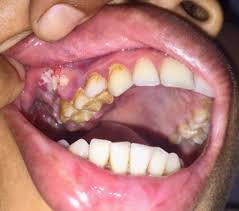

3. 구강암 초기 증상

구강암의 초기 증상은 다음과 같습니다.

- 입안의 궤양: 2주 이상 지속되는 통증 없는 궤양

- 구강 내 혹이나 덩어리: 만져지는 종괴